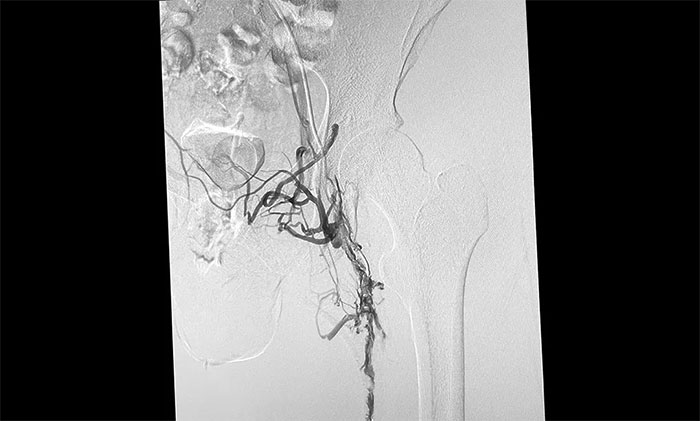

12月15日,席刚明教授在王贵平博士及介入团队协助下顺利行将一个形似伞状的人工滤器经患者右侧股静脉穿刺迅速置入肾静脉下方,“网”住了通往心血管和肺部的致命栓子,阻挡血液栓子进入肺动脉,及时挽救了患者生命。之后对病变血管进行了血栓抽吸术,及接触性溶栓,抽出了大量血栓,复查下肢造影示血栓基本消失,下肢静脉血管再通,整个手术顺利完成。术后,患者下肢肿胀好转。

▲ 下肢静脉血管顺利再通